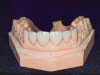

Figure 7. Crowns and veneers on model.

Figure 7